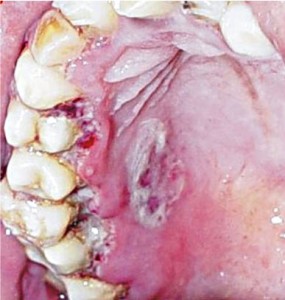

Клиническая картина. Стоматит язвенно-некротический Венсана может начинаться с недомогания, уменьшения слюноотделения и жгучей боли в деснах. На десневом крае некроз возникает в области верхушки межзубных увеличенных сосочков. Язва покрыта серовато-желтым налетом, при надавливании на сосочек кровоточит. Хорошо отграничена от здоровой слизистой оболочки. Некроз может поражать сосочек до собственно десны. Язвы в этом случае сливаются, образуя линейное изъязвление, очень болезненны, легко кровоточат. Определяется гнилостный запах изо рта. Язвы ретромолярной области (области третьих моляров), а также под протезами, на слизистой оболочке щек обычно возникают на фоне отечной гиперемированной слизистой, их края изрезанные, дно покрыто серым толстым налетом. Лимфатические подчелюстные узлы увеличены, болезненны. Возможно острое и хроническое течение заболевания.